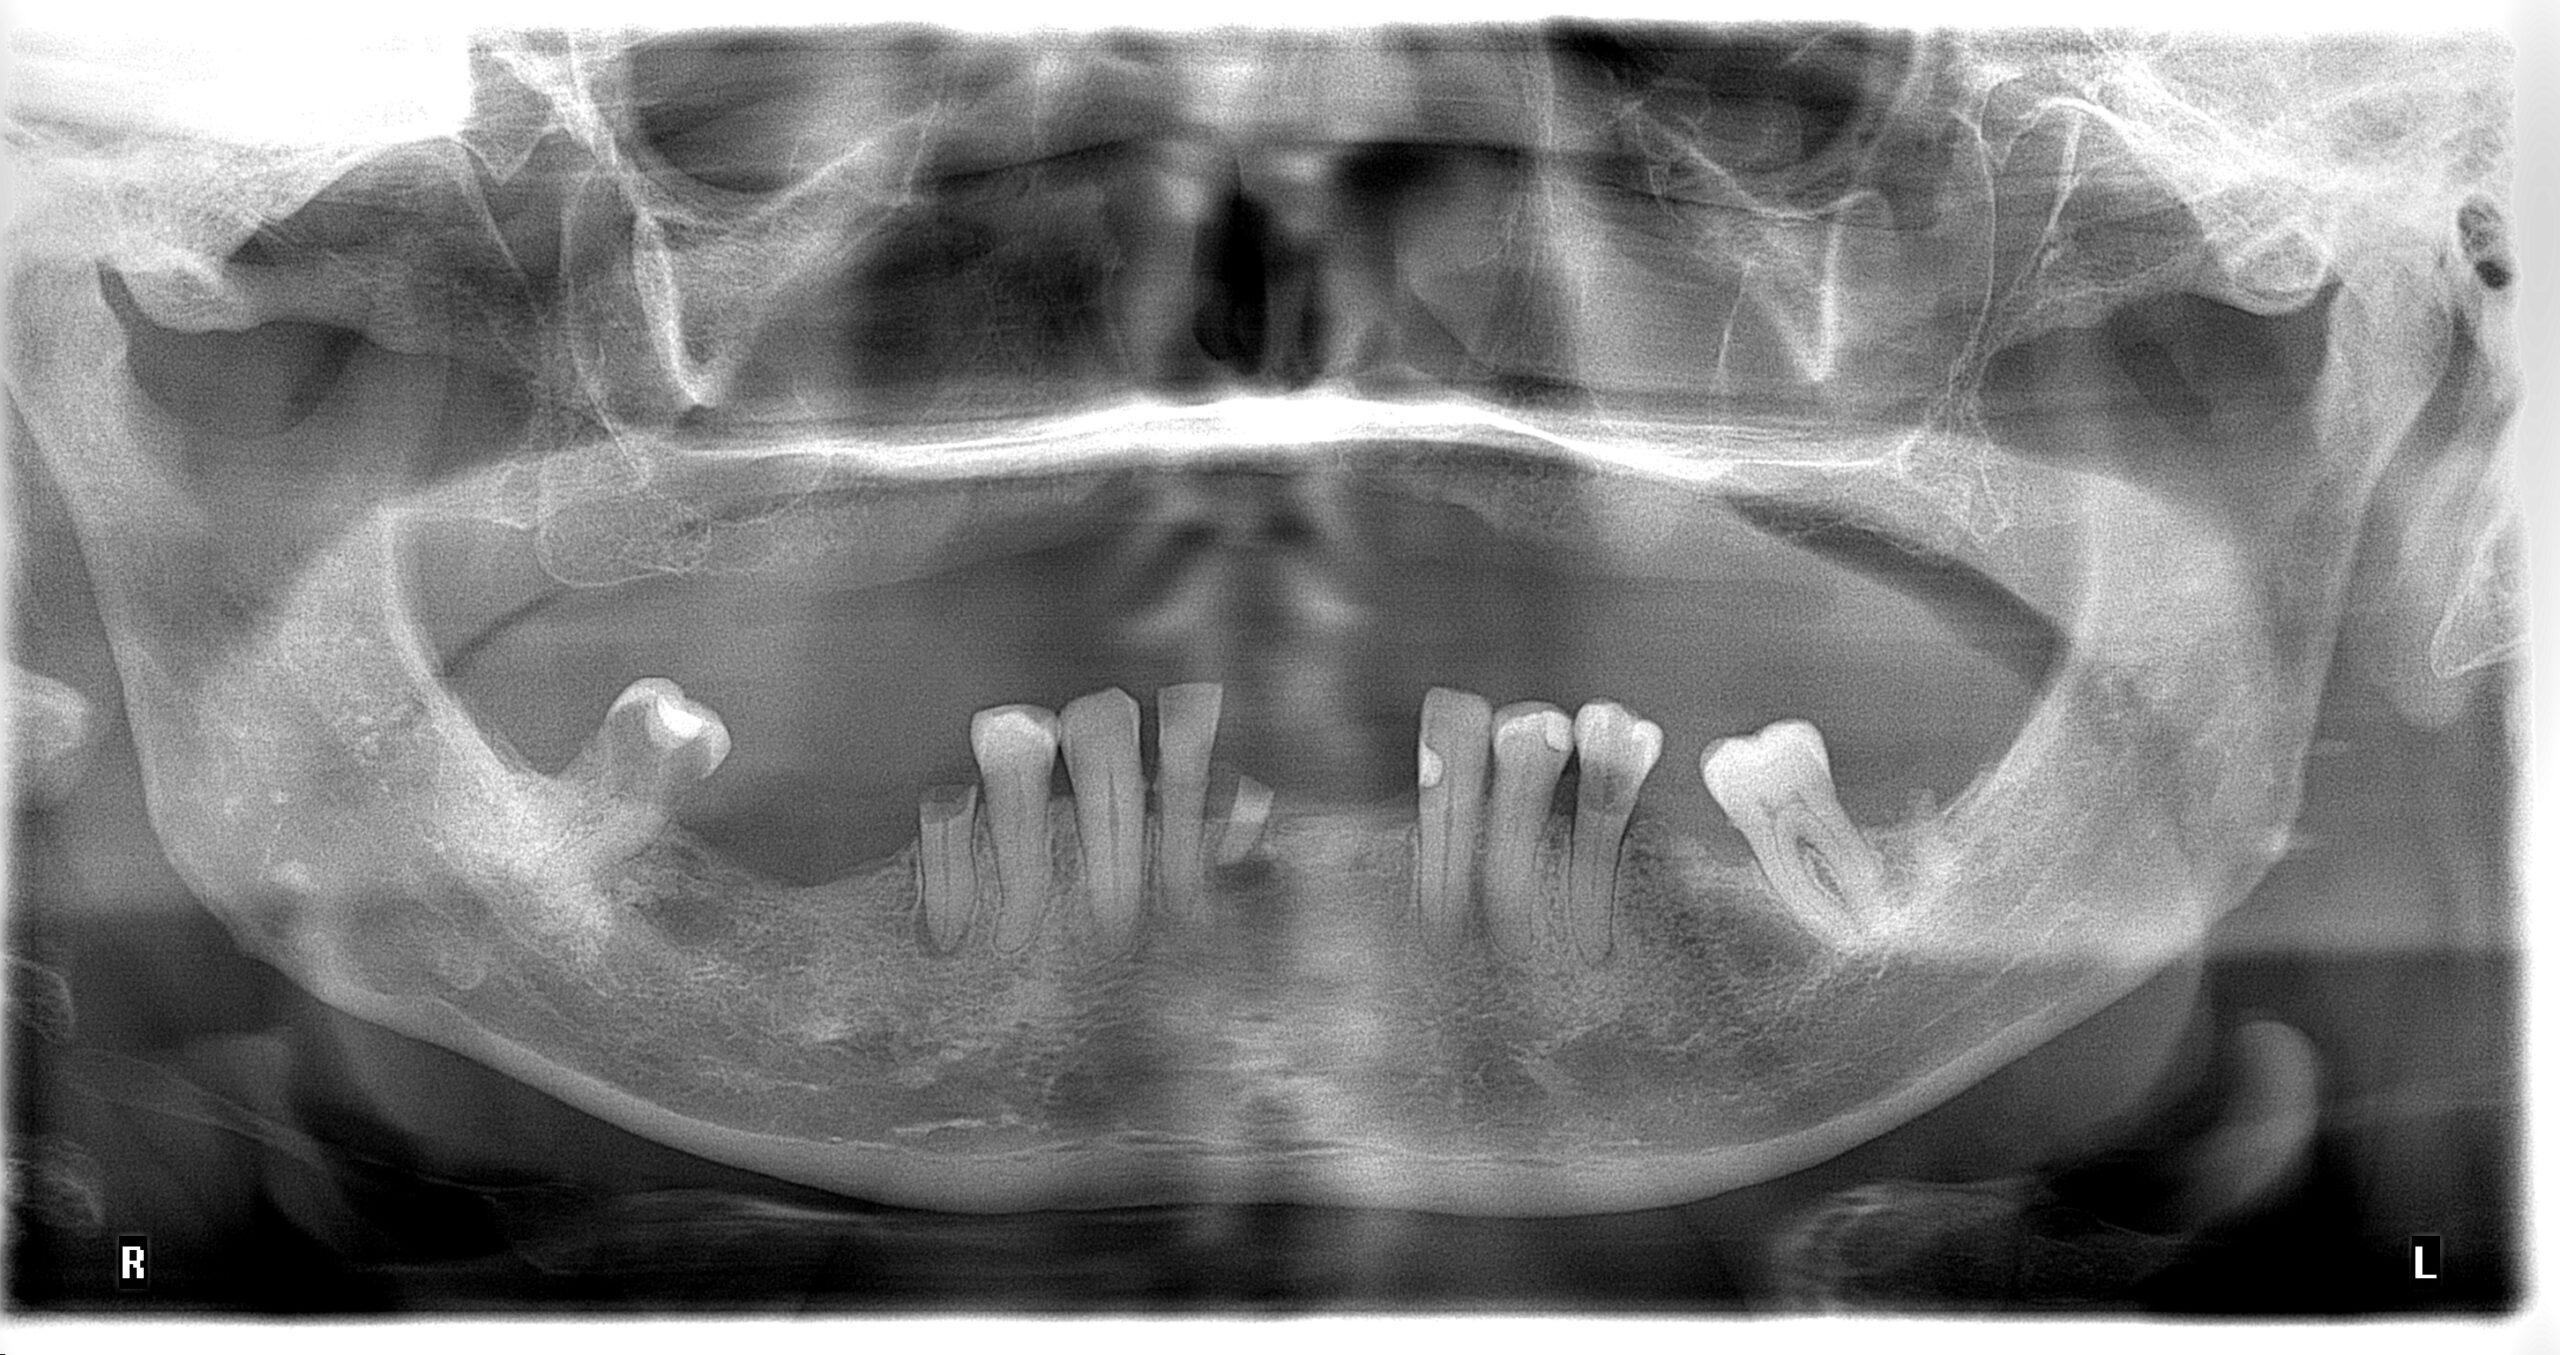

Radiografía panorámica dental en Medellín: La panorámica dental en Medellín es utilizada para tener una visión general del paciente ya que es posible evaluar en conjunto los dientes, el hueso alveolar, los maxilares y las estructuras anatómicas adyacentes, dando una visión detallada de la salud general del paciente

La radiografía panorámica ofrece una vista general del paciente, permitiendo evaluar dientes, hueso alveolar, maxilares y estructuras adyacentes para un diagnóstico integral.